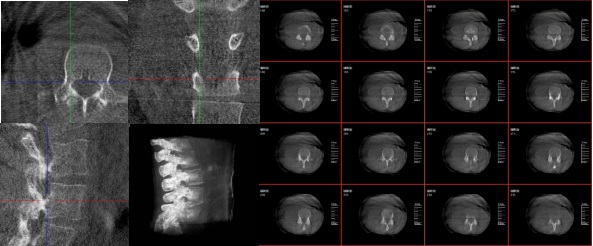

三維重建技術(shù)在醫(yī)學(xué)影像診斷領(lǐng)域十分重要,它是一種利用計算機(jī)軟件將二維醫(yī)學(xué)影像(如X光、CT、MRI等)轉(zhuǎn)化為三維立體圖像的技術(shù),可以為醫(yī)生提供更直觀、更清晰的圖像信息,方便醫(yī)生從多個角度觀察病灶,從而更全面地了解病情,有助于提高診斷的準(zhǔn)確性和效率。

6.可視化:將生成的三維模型以可視化的方式展示給醫(yī)生,幫助他們更好地理解患者的病情。

1.診斷疾?。和ㄟ^三維重建技術(shù),醫(yī)生可以更直觀、清晰地觀察到患者體內(nèi)的異常情況,如腫瘤、骨折等,從而更準(zhǔn)確地診斷疾病。

2.手術(shù)規(guī)劃:在手術(shù)前,醫(yī)生可以通過三維重建技術(shù)對患者的病變部位進(jìn)行詳細(xì)的觀察和分析,制定出最佳的手術(shù)方案。

3.手術(shù)導(dǎo)航:在手術(shù)過程中,醫(yī)生可以通過三維重建技術(shù)實時觀察手術(shù)器械的位置,提高手術(shù)的精確性和安全性。例如在關(guān)節(jié)外科手術(shù)中,存在植入物的錯位在術(shù)中不易發(fā)現(xiàn)的情況,如果在術(shù)后CT中檢查出,就不可避免地需要翻修手術(shù),這就會增加并發(fā)癥的概率以及感染風(fēng)險。而通過術(shù)中三維影像設(shè)備PLX C7600的檢查,可以立即發(fā)現(xiàn)植入物的錯位,減少不必要的第二次手術(shù)。